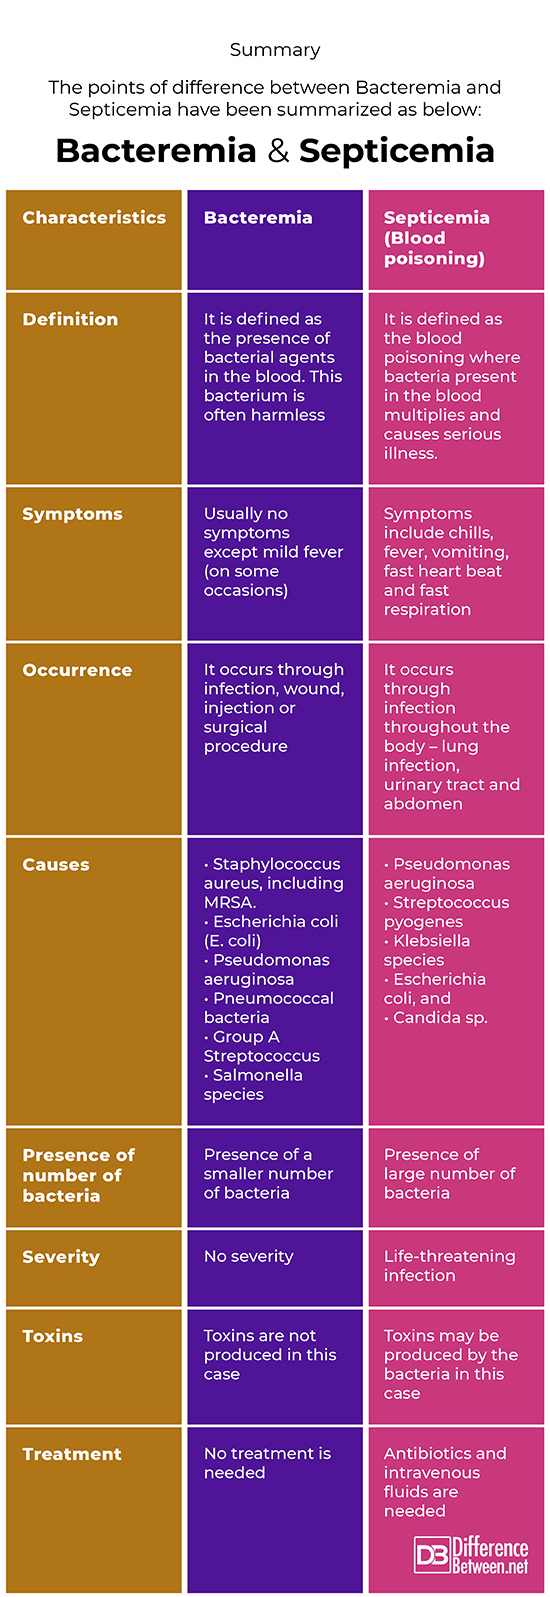

Summary

The points of difference between Bacteremia and Septicemia have been summarized as below:

Definition

Bacteremia

Curable bacterial infection in the blood stream – as harmless as vigorous tooth brushing. A small number of bacteria are noticed in this case removed by the body on its own. Occasionally, bacteremia progresses to dangerous infection called septicemia and sepsis.

Septicemia

The presence of Systemic Inflammatory Response Syndrome with an identifiable infection source. It is a clinical name for blood poisoning.

Symptoms

Bacteremia

Cases in this case are asymptomatic. People with stronger immune system will clear the bacterial without you even realizing it.

Septicemia

Causes

Causes of Bacteremia

Caused by Clostridium difficile, Pseudomonas, Staphylococcus, Hemophilus, E. coli, herpes, urinary tract infections, Streptococcus, peritonitis,

Causes of Septicemia

Staphylococci, are thought to cause more than fifty percent of cases of sepsis. Other bacteria include Pseudomonas aeruginosa, Streptococcus pyogenes, Klebsiella species, Escherichia coli, and even Candida sp.